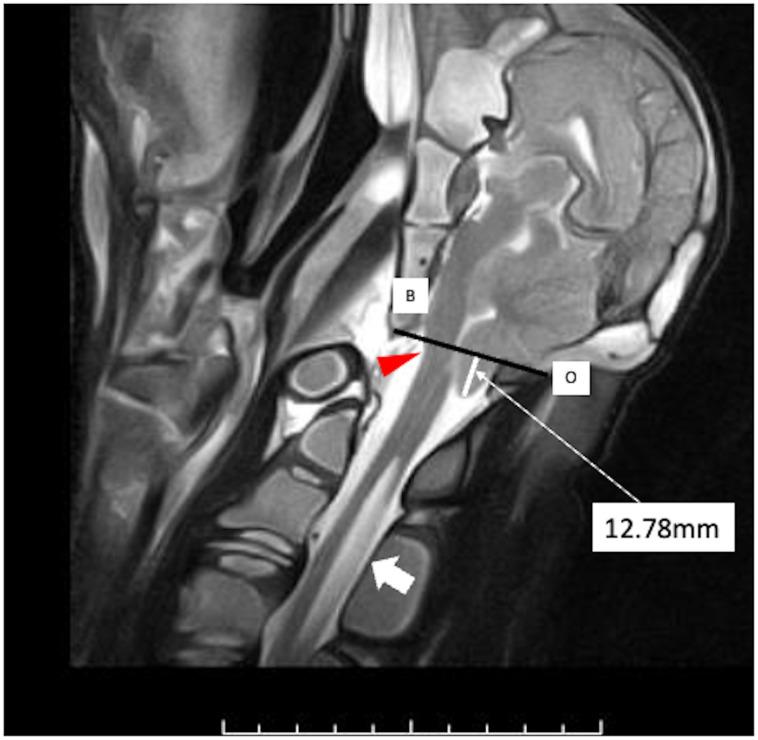

A 2-day-old male black calf presented with neurological symptoms, including opisthotonus. It was unable to stand due to hindquarter paresis. At 5 days old, the calf was able to stand, but exhibited a crossed forelimb gait. Computed tomography and magnetic resonance imaging revealed the expansion of the sutures between the squamous-lateral part of the occipital bone and between the occipital-temporal bone, cerebellar tonsillar herniation, posterior displacement of the brainstem, and cervical syringomyelia at 12 days old. This is the first case report of a live calf diagnosed with Arnold Chiari malformation classified as Chiari type 1.5 malformation in humans.

一只 2 日龄雄性黑色小牛出现了神经症状,包括角弓反张。由于后肢瘫痪,它无法站立。5 日龄时,小牛能够站立,但表现出前肢交叉步态。计算机断层扫描和磁共振成像显示,在 12 日龄时,枕骨鳞部与枕颞骨之间的缝扩张,小脑扁桃体疝出,脑干后移,颈段脊髓空洞症。这是首例在活牛中诊断出的人类 Chiari 畸形 1.5 型病例。